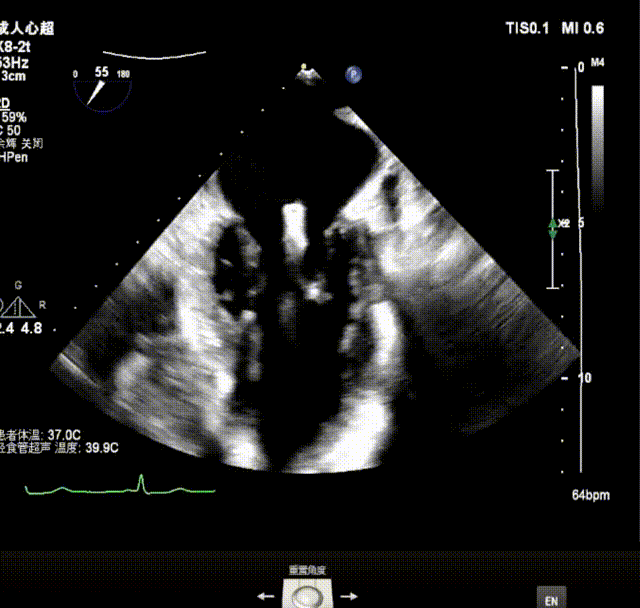

X-plane视窗可见二尖瓣病变区脱垂,重度偏心性返流.

X-plane视窗可见二尖瓣2区脱垂;3D enface view示二尖瓣内P2脱垂,偏心性返流